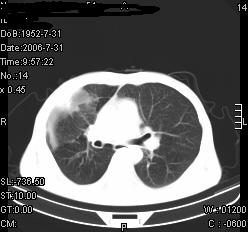

患者,男,54岁,咳嗦,咳痰20天。抗炎治疗2周。现esr76mm/h,目前患者症状明显好转,但发现两次ct片未见明显变化。两次分别做与7.25、7.31。第一次诊断右肺上叶炎症累计胸膜。大家看,从影像上内排除结核吗?

结核的可能性非常大,右上肺病变应该考虑干酪性肺炎。理由:

3.虽经抗炎治疗肺窗病灶有所吸收、减小,但纵隔窗病灶形态、密度、范围无明显变化。如果是单纯的大叶性肺炎,“抗炎治疗2周,目前患者症状明显好转”病灶应该基本消散了,至少也处于吸收消散期,密度变淡、范围变小。同时本病例所示其内的密度不均匀,见多发大小不一空洞样影也不符合大叶性肺炎吸收消散期表现。

病灶特点:片状 索条 结节混杂影,部分融合,密度不均,广泛累及相应胸膜.

临床治疗;二周未吸收.但症状好转.

多考虑:肺结核.